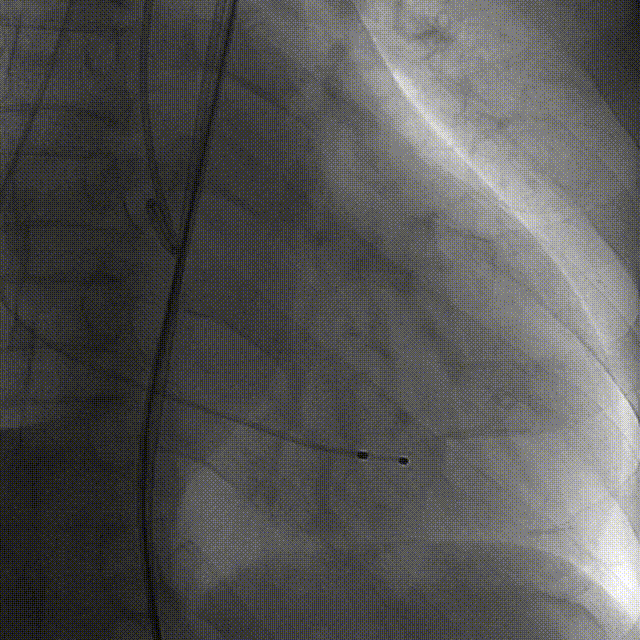

术前右窦中心造影

大鞘植入